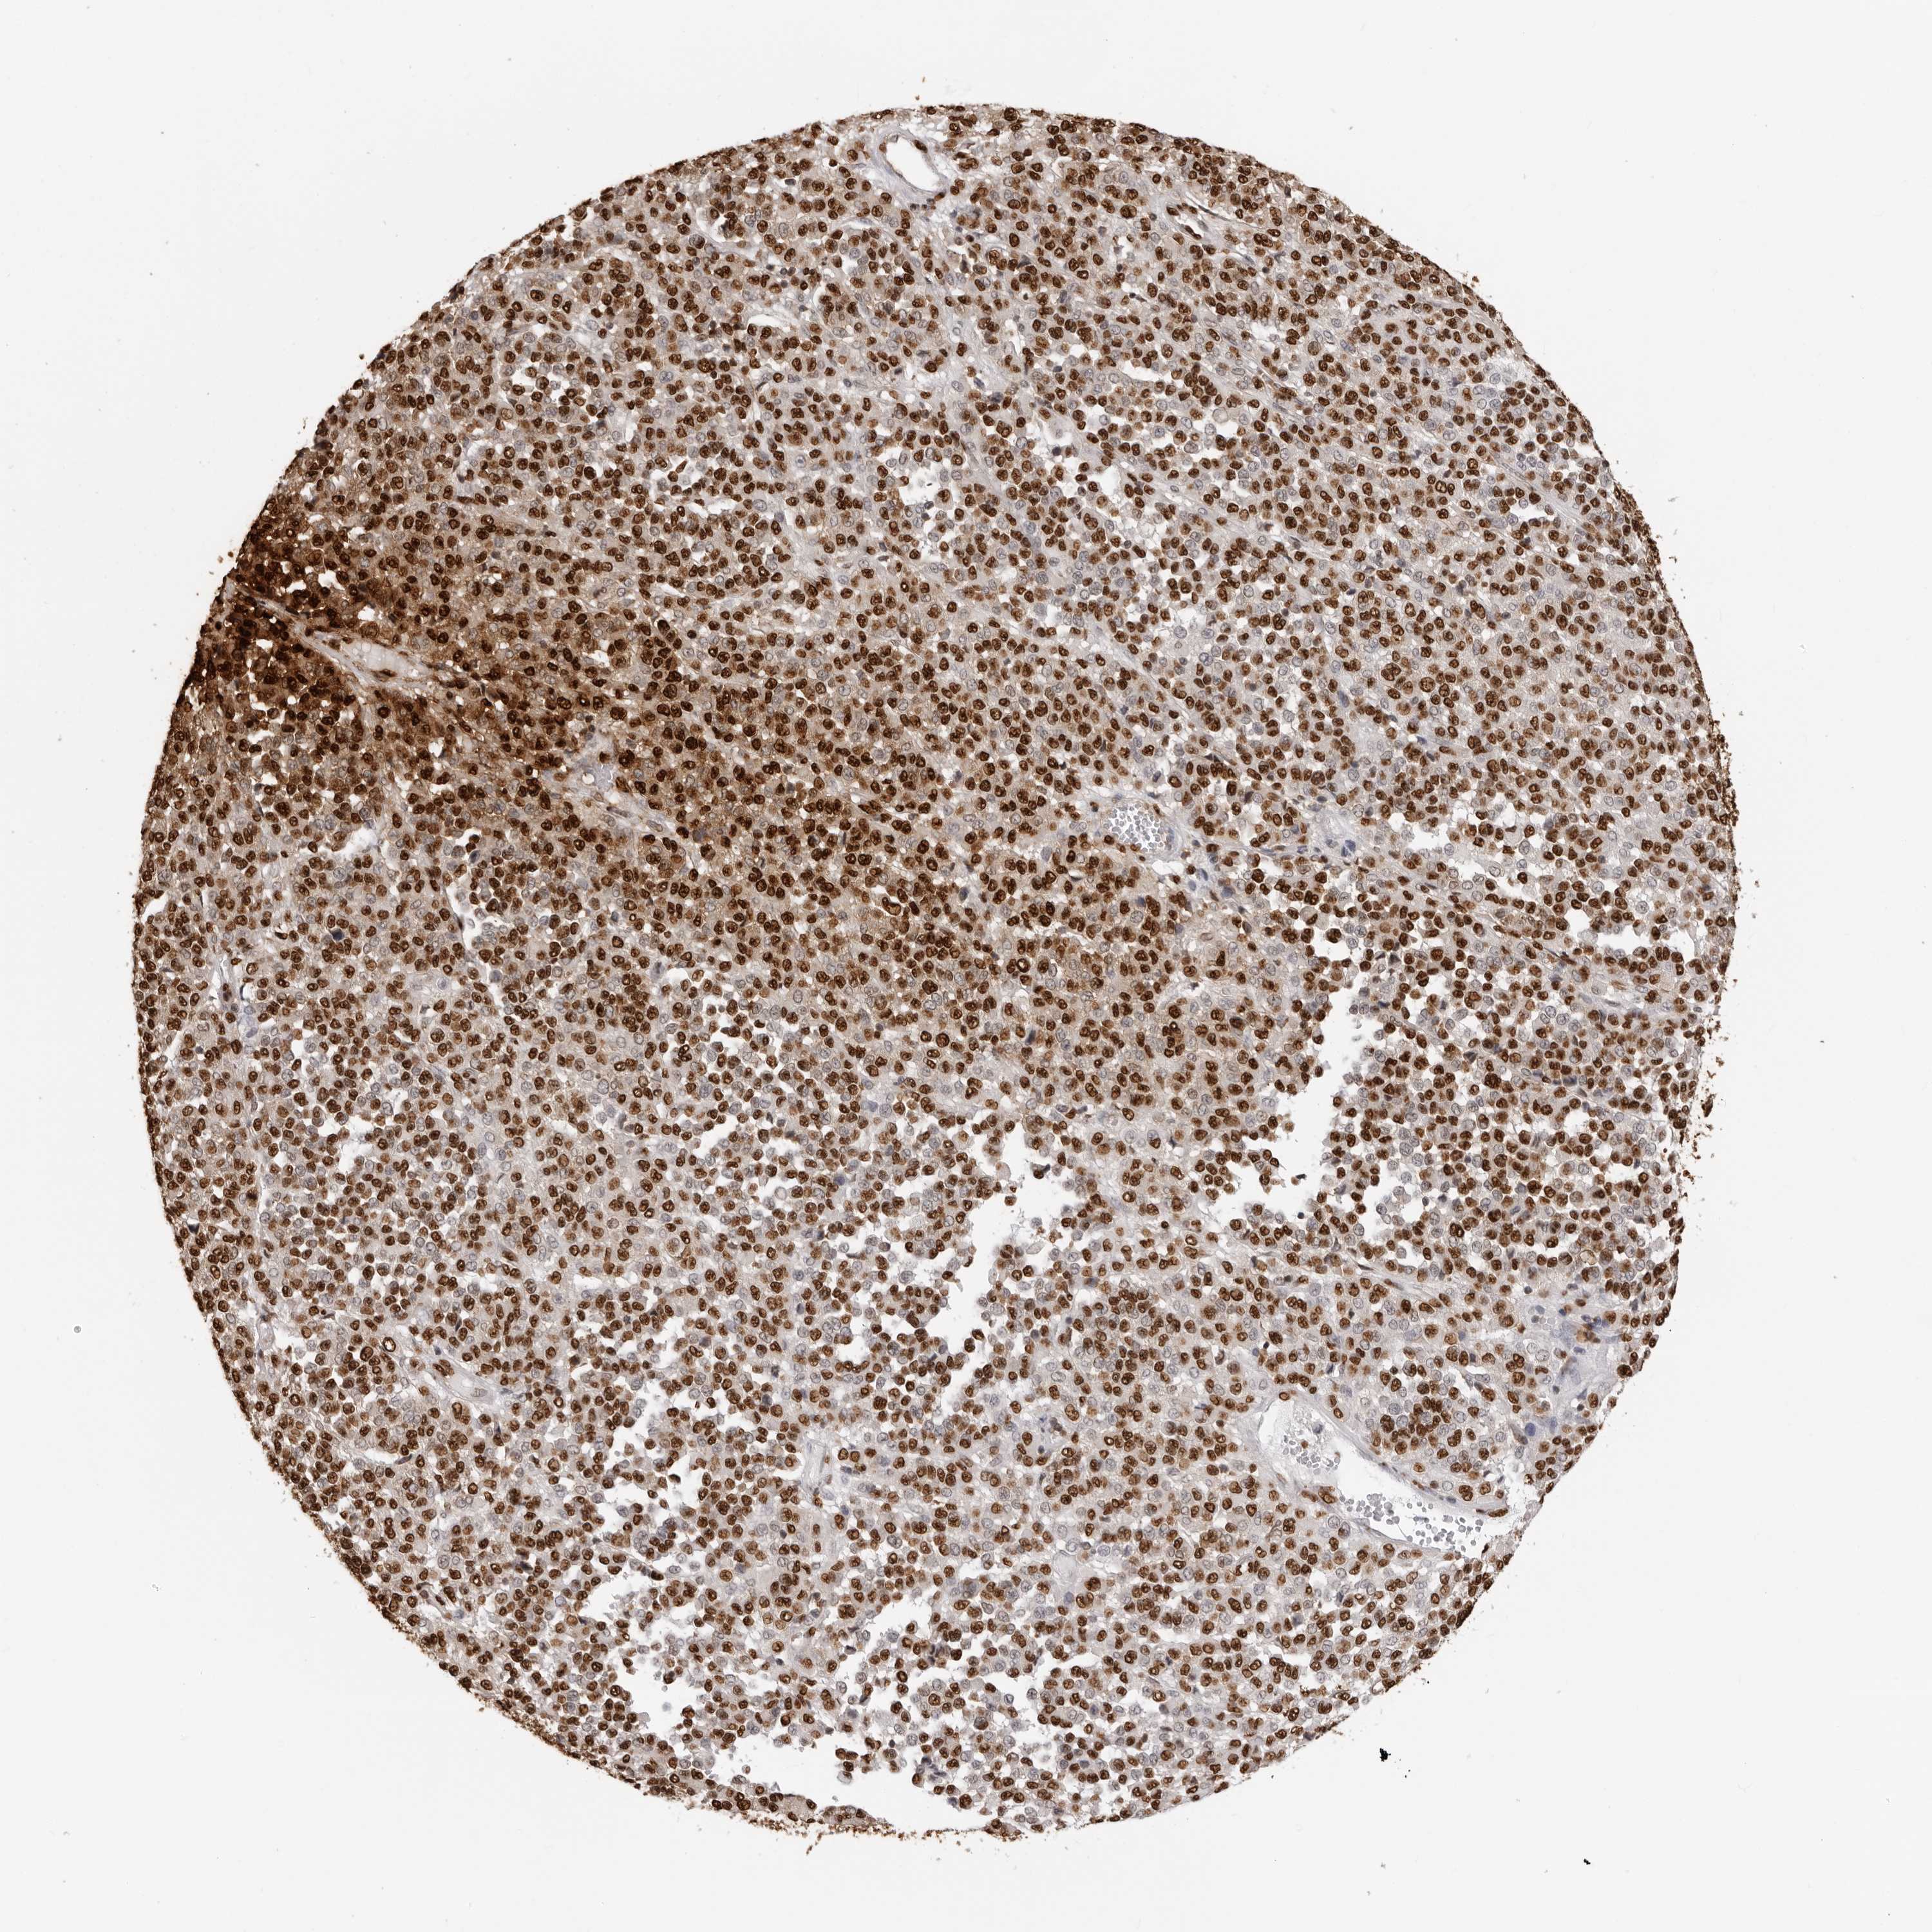

MELANOMA - Protein expressioni

A mouse-over function shows sample information and annotation data. Click on an image to view it in a full screen mode. Samples can be filtered based on level of antibody staining by selecting one or several of the following categories: high, medium, low and not detected. The assay and annotation is described here.

Note that samples used for immunohistochemistry by the Human Protein Atlas do not correspond to samples in the TCGA dataset.

Antibody stainingi

Antibody staining in the annotated cell types in the current human tissue is reported as not detected, low, medium, or high, based on conventional immunohistochemistry profiling in selected tissues. This score is based on the combination of the staining intensity and fraction of stained cells.

Each image is clickable and will lead to virtual microscopy that enables deeper exploration of all samples and also displays staining intensity scores, fraction scores and subcellular localization as well as patient and tissue information for each sample.

Antibody HPA024037

Antibody HPA065325

Antibody HPA074591

Antibody CAB025417

Staining

High

Medium

Low

Not detected

Intensity

Strong

Moderate

Weak

Negative

Quantity

>75%

75%-25%

<25%

None

Location

Nuclear

Cytoplasmic/membranous

Cytoplasmic/membranous,nuclear

Malignant melanoma, NOS

Malignant melanoma, Metastatic site